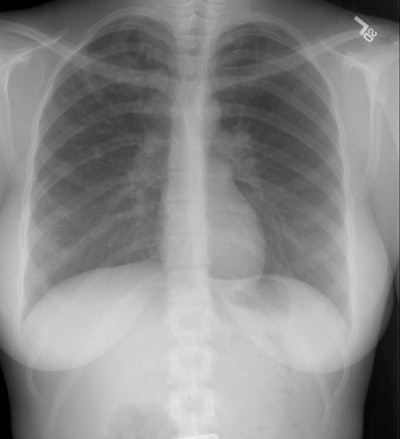

Cystic Fibrosis:

The chest radiograph below is on a 22 year old female patient with cystic fibrosis. The abnormalities are predominantly confined to the upper lobes- particularly the right upper lobe. Ring shadows, tram-tracking, and peripheral branching densities are all evident.

(Click image to magnify)